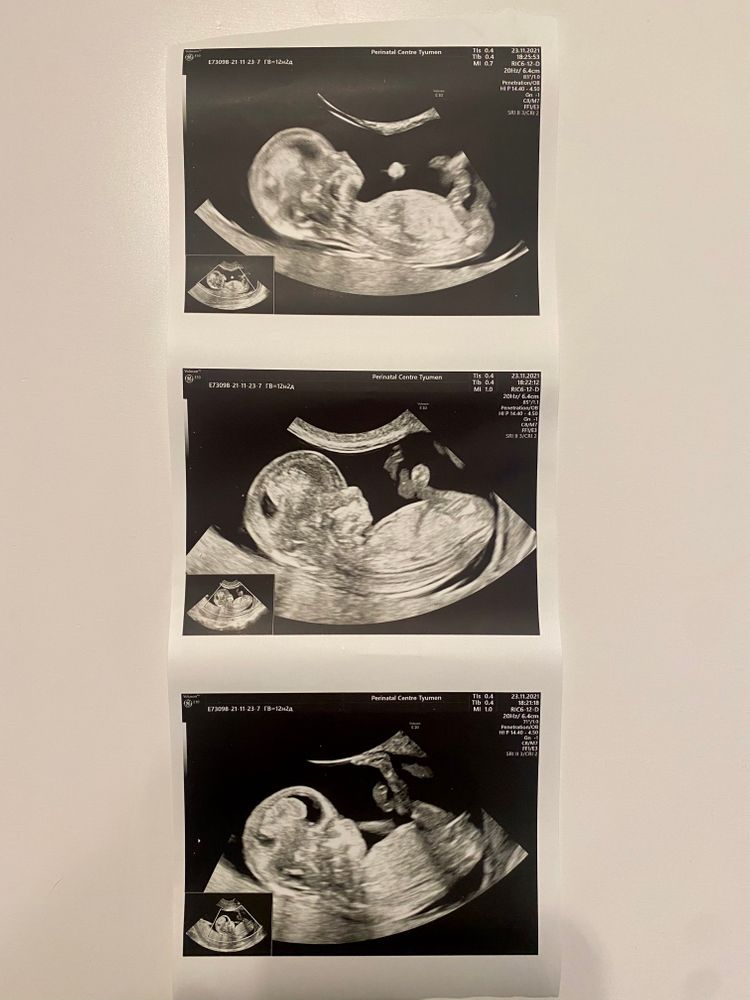

Девочки, привет. Врач на УЗИ пол не сказала, говорит «немного сомневаюсь, а это все-таки +700 рублей стоит» 😂 Кто что видит?) Интересно так 🤪

Если на послебнем фото показан половой уголок, то похоже на девочку)

Сомневалась ,наверное,так как ,как по мне ,по очертаниям черепа на мальчика похож . А если это половой бугорок на фото, то наклон на девочку.